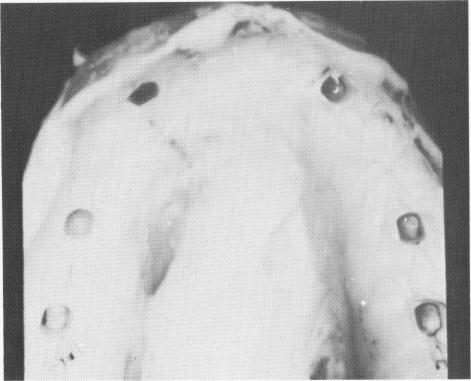

Fig. 12-80. The tissues were carefully sutured with mat-tress or purse-string suturing around each post, with interrupted surgical ties between them.

the second surgical incision is made directly over the original incision and the implant is set over the bone (Fig. 12-79). Purse-string sutures are placed around each protruding post. As many surgical ties and mattress sutures as are needed are placed between the four abutment posts (Fig. 12-80).

1 Mattress or purse string suturing around each maxillary post done